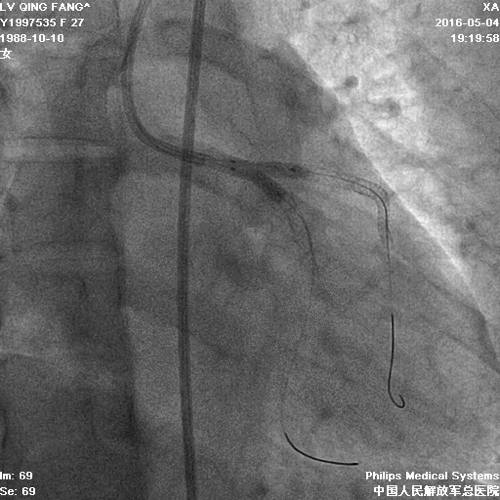

PCI